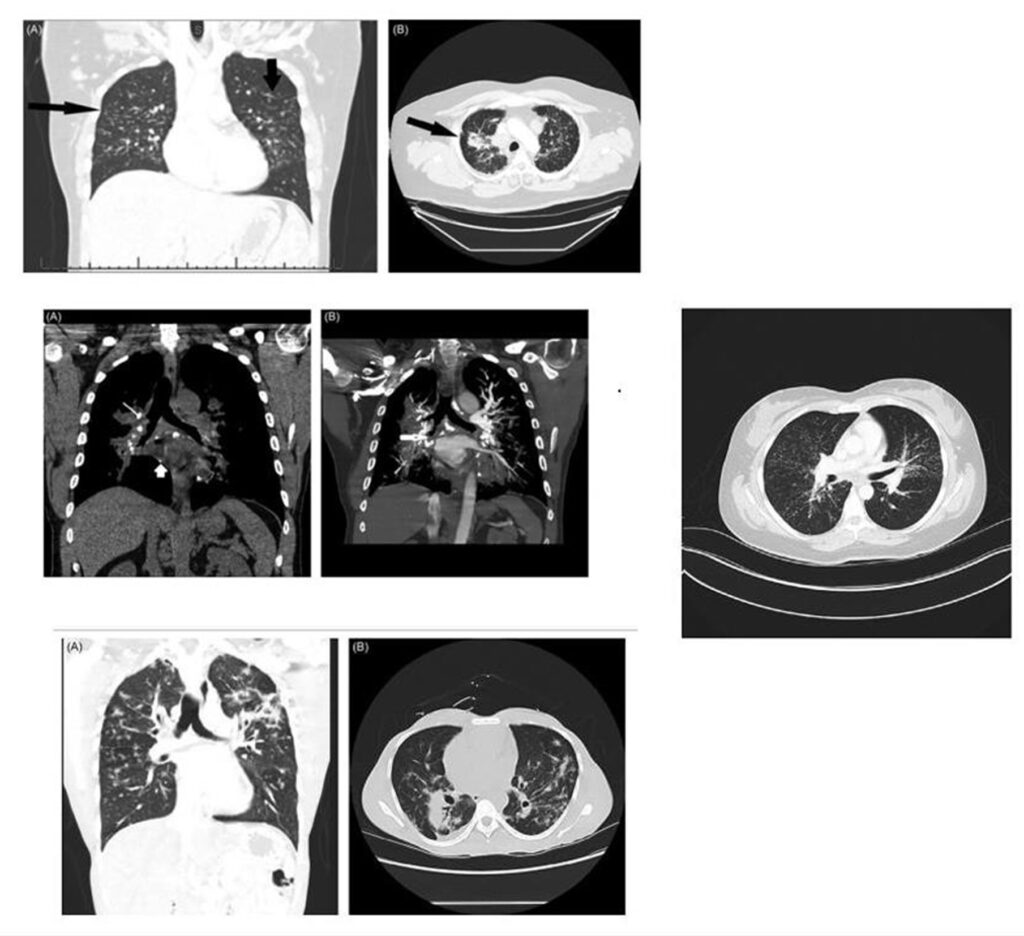

La sarcoidosis pulmonar se caracteriza por varios hallazgos en la tomografía computarizada de alta resolución (TCAR). Estos incluyen linfadenopatía hiliar y paratraqueal bilateral bien definida, opacidades nodulares y micronodulares con distribución perilinfática. Los nódulos son redondeados y suelen tener un tamaño de 2 a 4 mm. También se observa el agrandamiento y calcificación de los ganglios linfáticos hiliares bilaterales. Las calcificaciones pueden presentar diferentes aspectos, como amorfo, puntiforme (parecido a una palomita de maíz) o similar a una cáscara de huevo. La distribución perilinfática de las lesiones micronodulares es el patrón parenquimatoso más frecuente. Con el tiempo, estas lesiones pueden fusionarse y formar macronódulos y conglomerados similares a masas, con la presencia de pequeños nódulos satélites alrededor de las masas conglomeradas, lo que se conoce como “signo de galaxia”.

En la TCAR se pueden encontrar otros hallazgos menos frecuentes, como cambios fibróticos con opacidades lineales y bronquiectasias por tracción, opacidades parcheadas en vidrio esmerilado, consolidación parcheada del espacio aéreo (alveolitis sarcoide o sarcoidosis alveolar), opacidades reticulares lineales aisladas, halo inverso o signo del atolón. La sarcoidosis pulmonar también muestra un patrón de atenuación en mosaico debido a la afectación granulomatosa o fibrosis de las vías respiratorias pequeñas, lo cual puede estar asociado con obstrucción en las pruebas de función pulmonar. El atrapamiento de aire es común pero no específico de la sarcoidosis y puede estar presente en cualquier etapa radiográfica de la enfermedad. Se detectan anomalías traqueobronquiales en la TC, con engrosamiento y estenosis de la pared bronquial, que se correlacionan con los hallazgos broncoscópicos.

La estenosis bronquial puede ser causada por acumulación de granulomas endobronquiales, compresión extrínseca de las vías respiratorias debido a ganglios linfáticos agrandados en el mediastino, o distorsión de los bronquios debido a enfermedad parenquimatosa fibrótica en etapa terminal. El bronquio del lóbulo medio derecho es el más afectado en la sarcoidosis. En casos avanzados y de alto riesgo, la TCAR puede mostrar quistes fibróticos, ampollas y enfisema paracicatricial, que indican una etapa avanzada de la sarcoidosis. Estas lesiones tienden a afectar las zonas pulmonares superiores y medias, siguiendo las vías respiratorias más grandes en una distribución perihiliar. Los cambios quísticos subpleurales en panal se encuentran principalmente en las zonas pulmonares superiores y medias, mientras que las bases pulmonares se ven menos afectadas. Se debe considerar la fibrosis pulmonar idiopática en el diagnóstico diferencial cuando las bases pulmonares están involucradas.

En la tomografía computada de tórax en ventana pulmonar se identifica un patrón micronodular con distribución perilinfática y difusa en ambos hemitórax. Este hallazgo se acompaña de un engrosamiento peribronquial notable, así como de opacidades en vidrio deslustrado, que predominan en las zonas subpleurales y en las regiones posteriores de ambos pulmones.

En la tomografía computada de tórax en ventana mediastínica se observan múltiples adenopatías localizadas en diversas áreas del cuello y mediastino. Estas adenopatías se distribuyen en las cadenas yúgulo-carotídeas, en ambas regiones supraclaviculares y a lo largo del mediastino, abarcando específicamente las siguientes áreas: la región paratraqueal superior derecha, los espacios retrocavo-pretraqueal y prevascular, la zona subcarinal, la ventana aortopulmonar y en la región de la arteria mamaria (AM). La presencia de estas adenopatías sugiere un compromiso linfático difuso en estas zonas.